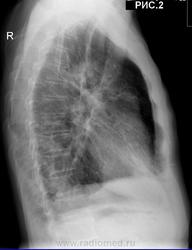

Пациент 74 г. Поступил с диагнозом ИБС: мерцательная аритмия...Инженер. Профанамнеза нет. Туберкулезом не болел. Неднократно последние 10 лет обследовался в ПТД. МБТ (-). Жалобы на одышку при физической нагрузке. Кашль, мокрота отсутствуют. Температура тела нормальная. Кровь: лейк.7,6*109/л, Эр.3,9, Нв-131г/л, НСТ-38%, Тромб.213, п-я.2%, сег.52%, лим.35%, м.8%. СОЭ-40 мм/ч. Рентгенограммы  грудной клетки (рис.1, рис.2) от 30.5.11. КТ  грудной клетки от 23.10.2010 г. см. ниже в комментариях. С уважением Nikolas

К метатуберкулёзным изменениям отнёс бы плевроапикальные наложения. Возможно, в верхушках есть и мелкие очаги, но разрешение репродукций… не очень.

Всё остальное – признаки хронического неспецифического. Бронхоэктазы в базальных сегментах весьма вероятны, особенно справа, но опять же, недостаточно видна структура лёгочного рисунка. Это фон. На этом фоне в верхней доле правого легкого, по-видимому, есть пневмония, и в нижней не исключается. Сердце не лёгочное. Плевродиафрагмальные спайки справа.

В средних и нижних отделах обоих лёгочных полей (больше справа) лёгочный рисунок усилен и деформирован по сетчатому типу, справа на этом фоне не исключается наличие инфильтрации нижней доли (ну или снижение прозрачности, возникает большое желание написать по типу "матового стекла) Плотные линейные тени пневмофиброза. Плеврофиброзные изменения.

Распространённые пневмо, плеврофиброзные изменения. Не исключается н/долевая пневмония справа (диф DS с интерстициальным пневмонитом).